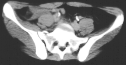

Radiographs:

Radiographs revealed a vertical buckle fracture of the right inferior sacrum, oblique fractures of the superior and inferior rami on the right and a fracture through the medial acetabulum. Obturator and iliac oblique inlet and outlet pelvic views, and a thin cut CT with 3-D reconstruction of the acetabulum were performed. These elucidated a comminuted anterior wall with fracture line extending to the posterior column. The posterior column was non-displaced. The pelvic fracture was non-displaced.

Assessment:

1. Right T-shaped acetabular fracture with anterior wall comminution.